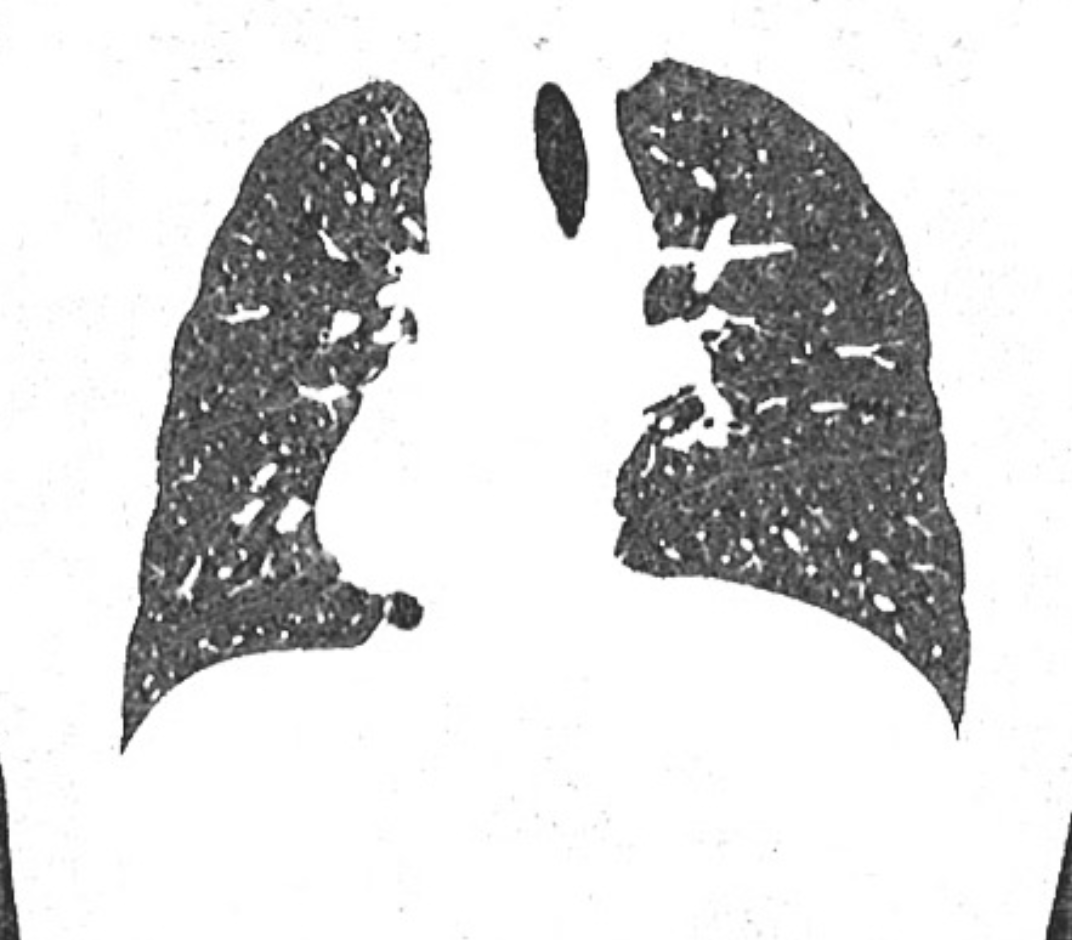

A similar process occurring in the thorax is called thoracic splenosis. It is rare and presents as multiple pleurally-based nodules in the left hemithorax. It typically occurs following blunt trauma causing a combination of splenic injury and left diaphragmatic rupture 4.